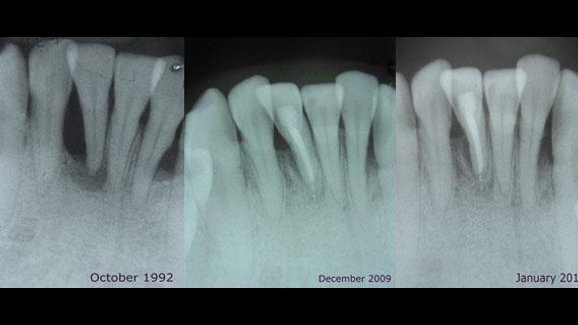

图为患有严重牙周炎患者在治疗前后的牙列影像对比图。 (Photo: Dr. Howard Tenenbaum)